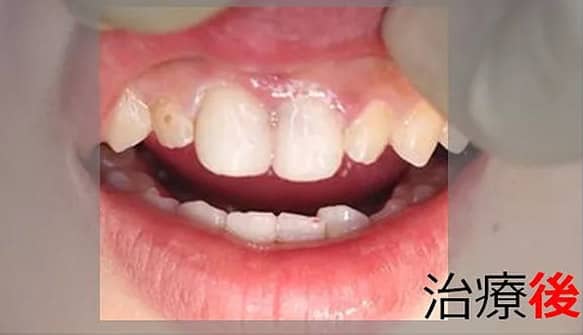

1矯正・マウスピース【治療例1】

治療後